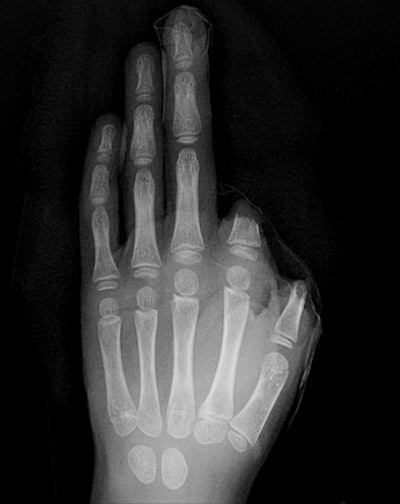

![]() |

| Finger amputation: Hand radiograph of a 7-year-old boy with an ATV injury who sustained traumatic amputation of the left thumb and index finger at the scene of the accident. |